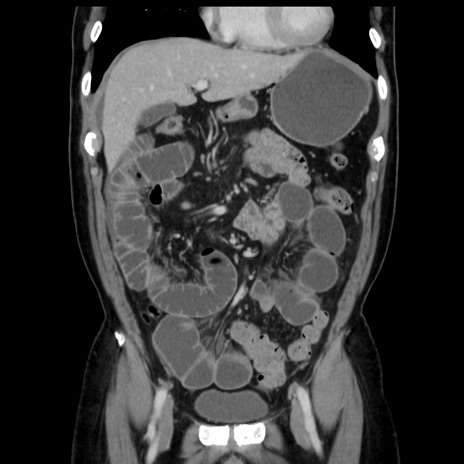

症例16(冠状断像)

【症例】 70歳代男性

【主訴】 腹痛、嘔吐

【現病歴】 約1ヶ月前より間欠的に腹痛と嘔吐あり、当院消化器内科を受診したところCTで多発する肝臓のLDAを指摘され、精査中であった。以降は消化器症状は安定していたが、2日前より嘔気と腹痛があり、同日より排便・排ガスが消失した。改善認めず、 本日、救急外来を受診した。

【既往歴】 大腸ポリープ切除後。

【身体所見】意識清明・会話良好、BT 36.3℃、BP 127/80mmHg、 P 80bpm、腹部:膨満あり、平坦・軟、上腹部正中および下腹部正中に圧痛あり、反跳痛なし、筋性防御なし。

【データ】WBC 7200、CRP 0.77